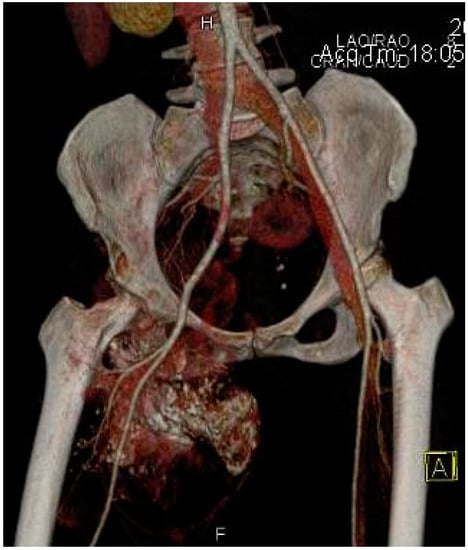

2.2. Imaging Examinations